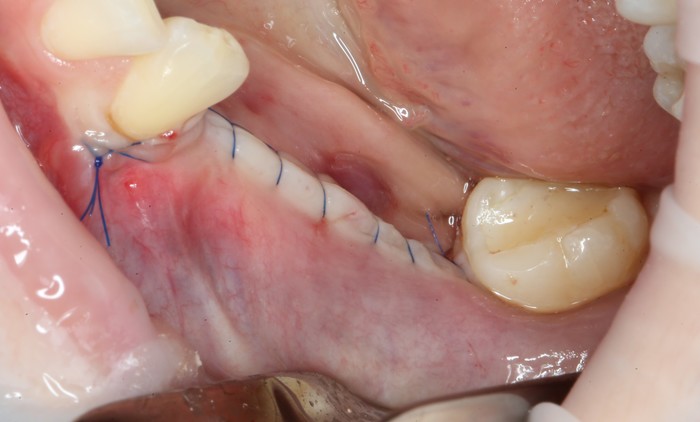

Уже на следующий день была запланирована имплантация.

Дабы не перегружать вас обилием одинаковых картинок, я оставлю один рентгеновский снимок, но отмечу, что установка имплантатов на верхней и нижней челюсти проводилась с разницей в 10 дней.

На верхней челюсти было дополнительно удалено два боковых резца с одномоментной установкой имплантатов, так же они были установлены в области четверок и шестых зубов. Дополнительно было проведено наращивание костной ткани - двусторонний синус - лифтинг. О том, что это такое, можно почитать ТУТ и ТУТ.

После нехитрых манипуляций мы прощаемся с Русланом на 4 месяца.